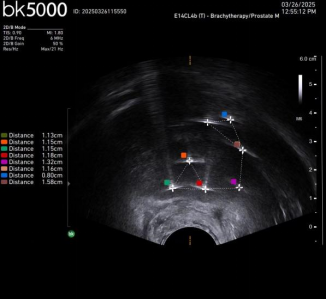

Case1. 超声定位电针穿刺及消融后改变